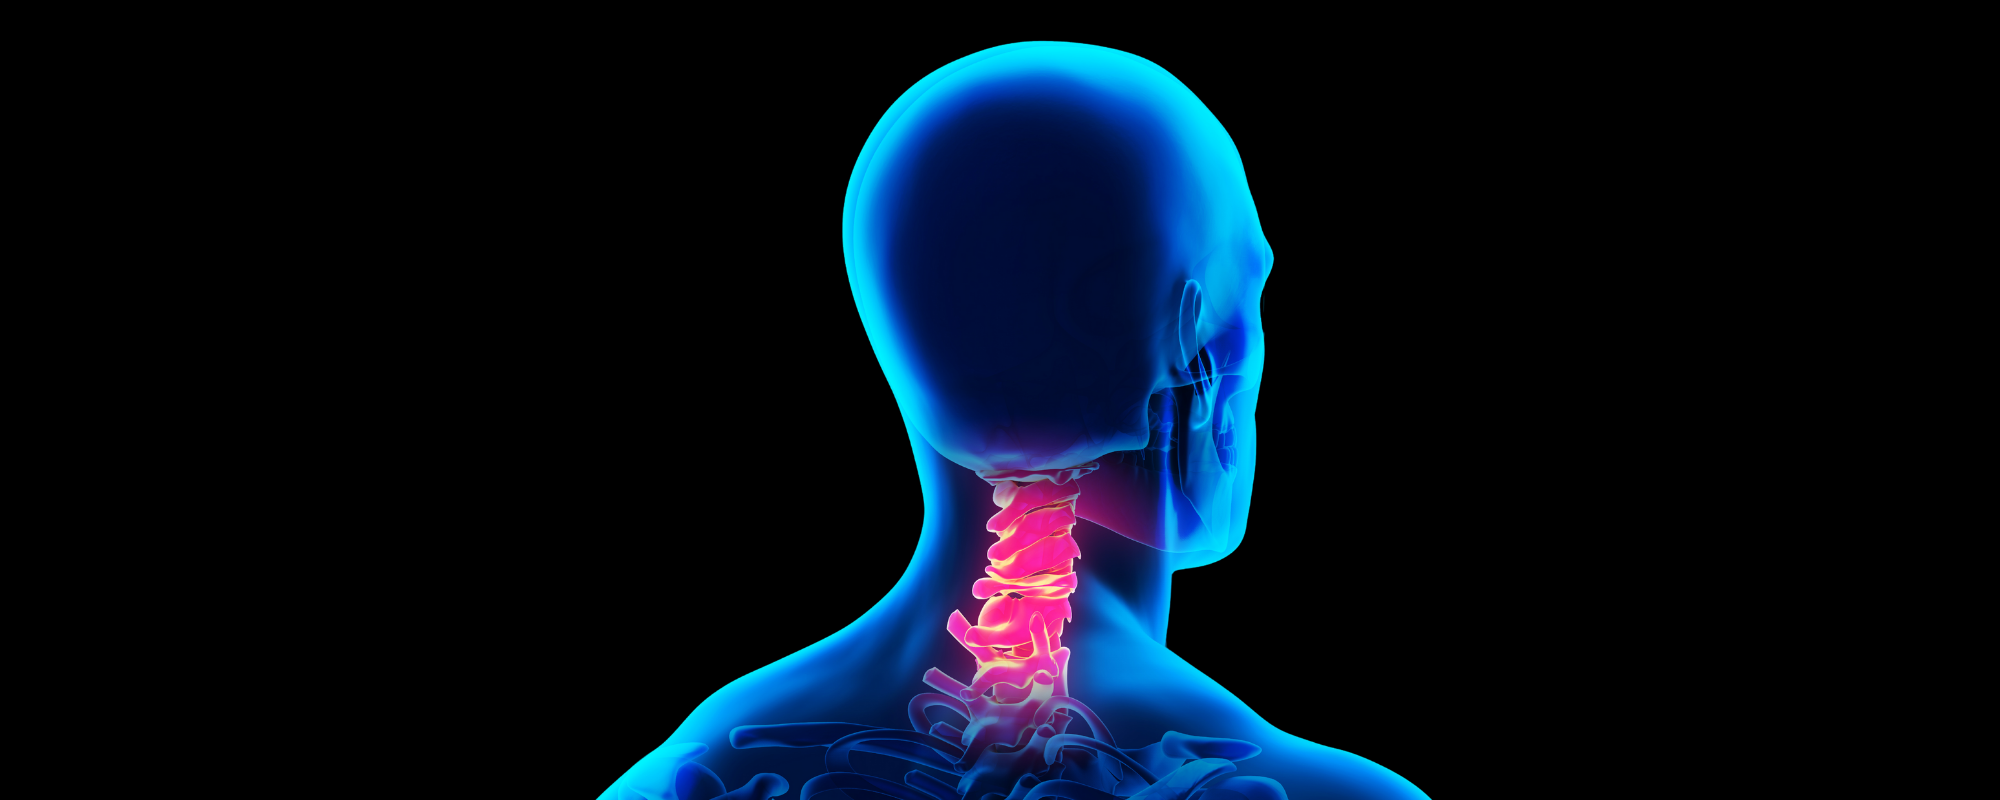

Servikal Spondiloz Nedir?

Servikal Vertebra (Servikal Omur) Nedir?